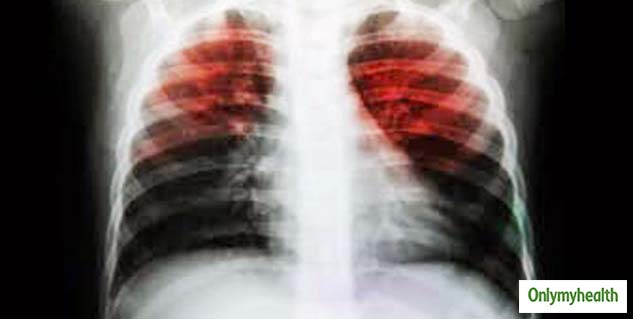

टीबी एक संक्रामक रोग है जो मुख्य रूप से फेफड़ों को प्रभावित करता है। ट्यूबरक्युलोसिस (Tuberculosis) बैक्टीरिया के कारण टीबी का रोग होता है, ये एक ऐसी संक्रमण रोग है जो एक इंसान से दूसरे इंसान को रोगी बना सकता है। टीबी के मरीज के खांसने और छींकने के दौरान मुंह और नाक से अनजाने में बूंदे निकल जाती है जिसके कारण ये संक्रमण फैलता है। इसका इलाज कराना बहुत जरूरी होता है, इस स्थिति में लापरवाही करने से मरीज की जान भी जा सकती है।

टीबी का रोग माइकोबैक्टीरियम ट्यूबरकुलोसिस (Tuberculosis) नामक एक बैक्टीरिया के कारण होता है। टीबी के अलग-अलग प्रकार हैं, और कुछ दवा के लिए प्रतिरोधी बन गए हैं। टीबी के बैक्टीरिया हवा में संक्रमित बूंदों के माध्यम से एक से दूसरे इंसान में प्रवेश कर सकते हैं। एक बार जब वे हवा में होते हैं, तो पास के एक-दूसरे व्यक्ति उन्हें सांस के जरिए अंदर ले जाते हैं जिसके कारण उनके शरीर में ऐसे बैक्टीरिया पहुंच जाते हैं और वो भी टीबी जैसी खतरनाक बीमारी का अनजाने में शिकार हो जाते हैं। इसके कई और भी कारण हो सकते हैं जैसे: छींक आना और खांसना।